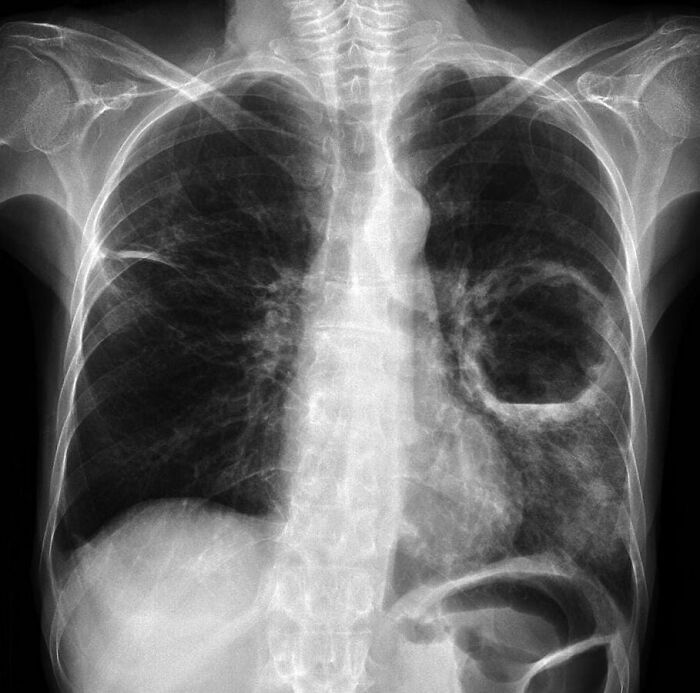

#4

Chest x-ray of a patient demonstrates a large left sided pulmonary cavity with a small dependent air-fluid level within the left mid zone, in keeping with pulmonary abscess. Patchy airspace opacification more inferiorly within left lower zone.

Scarring/atelectasis within lateral aspect of right upper zone.